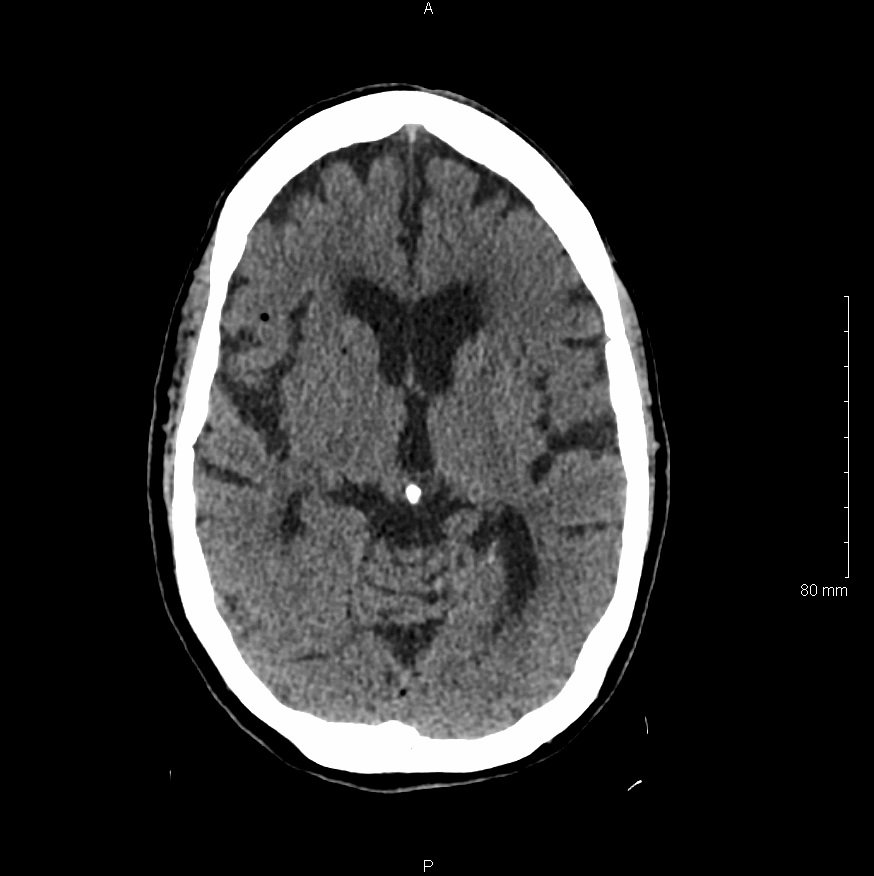

Physical examination revealed an obtunded female with sonorous respirations who withdrew from painful stimuli. Her blood pressure was 169/100 mm Hg, her heart rate was 104/min, and her respiration rate was 21/min. Further neurological examination identified left sided facial droop, left horizontal gaze palsy, and positive Babinski sign. Rapid sequence intubation was performed and a code stroke was called. The patient underwent diagnostic non-contrast computed tomography which revealed diffuse hypodense lesions consistent with an air embolism.

Significant findings:

Non-contrast head computed tomography (CT) demonstrates multifocal bilateral hypodense lesions (white arrows) representing air emboli. Note the lesions are located in the intra-axial distribution which indicates an underlying vascular origin.